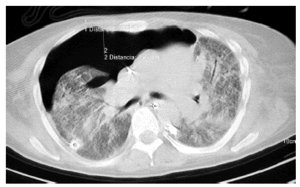

Se trata de una mujer de 36 años con antecedentes de hemosiderosis pulmonar idiopática que ingresa en la Unidad de Cuidados Intensivos (UCI) por insuficiencia respiratoria aguda secundaria a hemorragia alveolar. Es intubada y conectada a ventilación mecánica. A la semana de su ingreso se mantiene un deterioro grave del intercambio gaseoso (PaO2/FiO2 < 100), con infiltrado alveolar bilateral y sin evidencia de nuevo sangrado alveolar. Es diagnosticada de síndrome de distrés respiratorio del adulto secundario a hemorragia alveolar. A los 10 días la paciente sufre neumotórax bilateral y recidivante durante 21 días, a pesar de la colocación de 5 tubos de drenaje torácicos (fig. 1). Se realiza una tomografía computarizada (TC) de tórax en la que se evidencia neumotórax anterior derecho, con desplazamiento de mediastino, con neumatoceles diseminados y lesión difusa alveolointersticial bilateral (fig. 2). La paciente falleció en situación de hipoxemia refractaria tras 45 días de ingreso en UCI.

Fig. 2